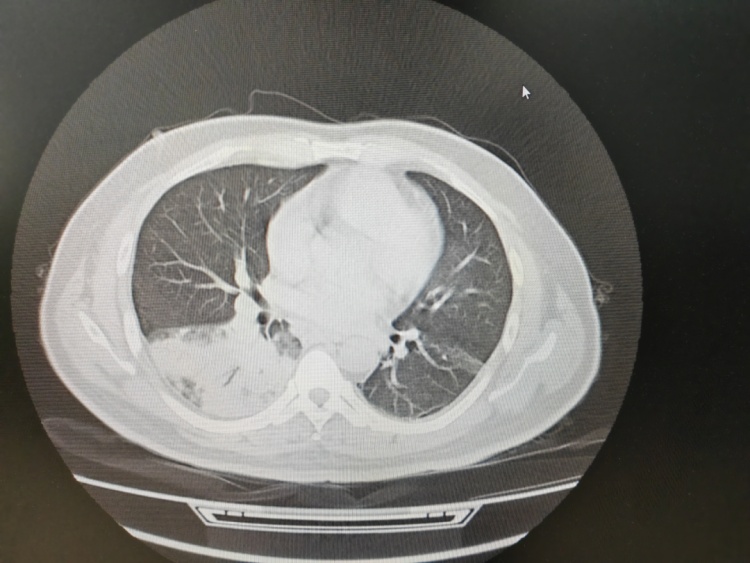

医生详细询问,并为患者完善了相应检查。结果显示,张先生的左肺竟然“白”了一大片。气管镜检查后,团队再通过肺泡灌洗液NGS检测抓住元凶——军团菌。